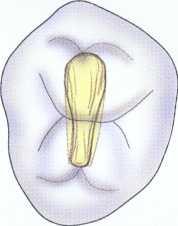

Maxillary Molars

Treatment of maxillary molars is never routine (Figure 2-22). In a recent study of maxillary first and second molars an MB2 canal was found in 96% of the mesiobuccal roots of maxillary first molars and 94% of the maxillary second molars. Approximately 54% were located in the traditional access opening, 31% were found with the use of a bur, and 10% were found with the aid of a microscope. The MBZ canal orifice was found on average 1.82 mm lingual to the main MB canal orifice.9 In another study of the maxillary first molar using microscopy, the MB Z canal was located in

93% of first molars and 60% of second molars4 (Figures 2-23 and 2-24). The difficulty in access, high percentage of fourth and even fifth canals, and root curvatures put even the "routine" maxillary molar in a high-risk category.3 Complicating factors such as limited opening, crowns, changes in tooth angulation, tooth position, and calcification make predictable treatment of these teeth challenging for even the most experienced clinician trained in microscopy, ultrasonics, and rotary instrumentation.

Guidelines for canal location in the maxillary first molar (Figure 2-25) differ from that in the maxillary second molar. In the maxillary first molar the MB canal is located under the mesial buccal cusp (see Figure 2-25, D). The MBZ canal is located mesial to a line from the

MB canal toward the palatal canal (see Figures 2-25, E, and 2-26). The DB canal is located distal to the MB canal in the buccal groove area, slightly lingual to the MB canal (see Figure 2-25, G). The palatal canal is generally the largest canal and is located under the mesiolingual (ML) cusp (see Figure 2-25, F). These general locations remain the same as the pulp calcifies with age (Figure 2-27). Although these general principles apply to the maxillary second molar, the chamber may be narrower, resembling a straight line (see Fig. 2-55).